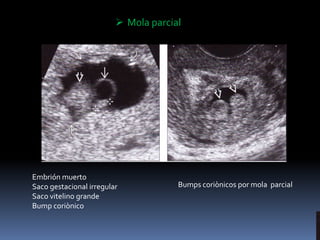

Parcial

El tejido anormal proviene de ambos padres

pero con incorrecta dotación genética

Restos de placenta e incluso un pequeño feto

atrófico

 Mola parcial

Embrión muerto

Saco gestacional irregular

Saco vitelino grande

Bump coriònico

Bumps coriònicos por mola parcial

 Mola parcial Embriónmuerto Saco gestacional irregular Saco vitelino grande Bump coriònico Bumps coriònicos por mola parcial